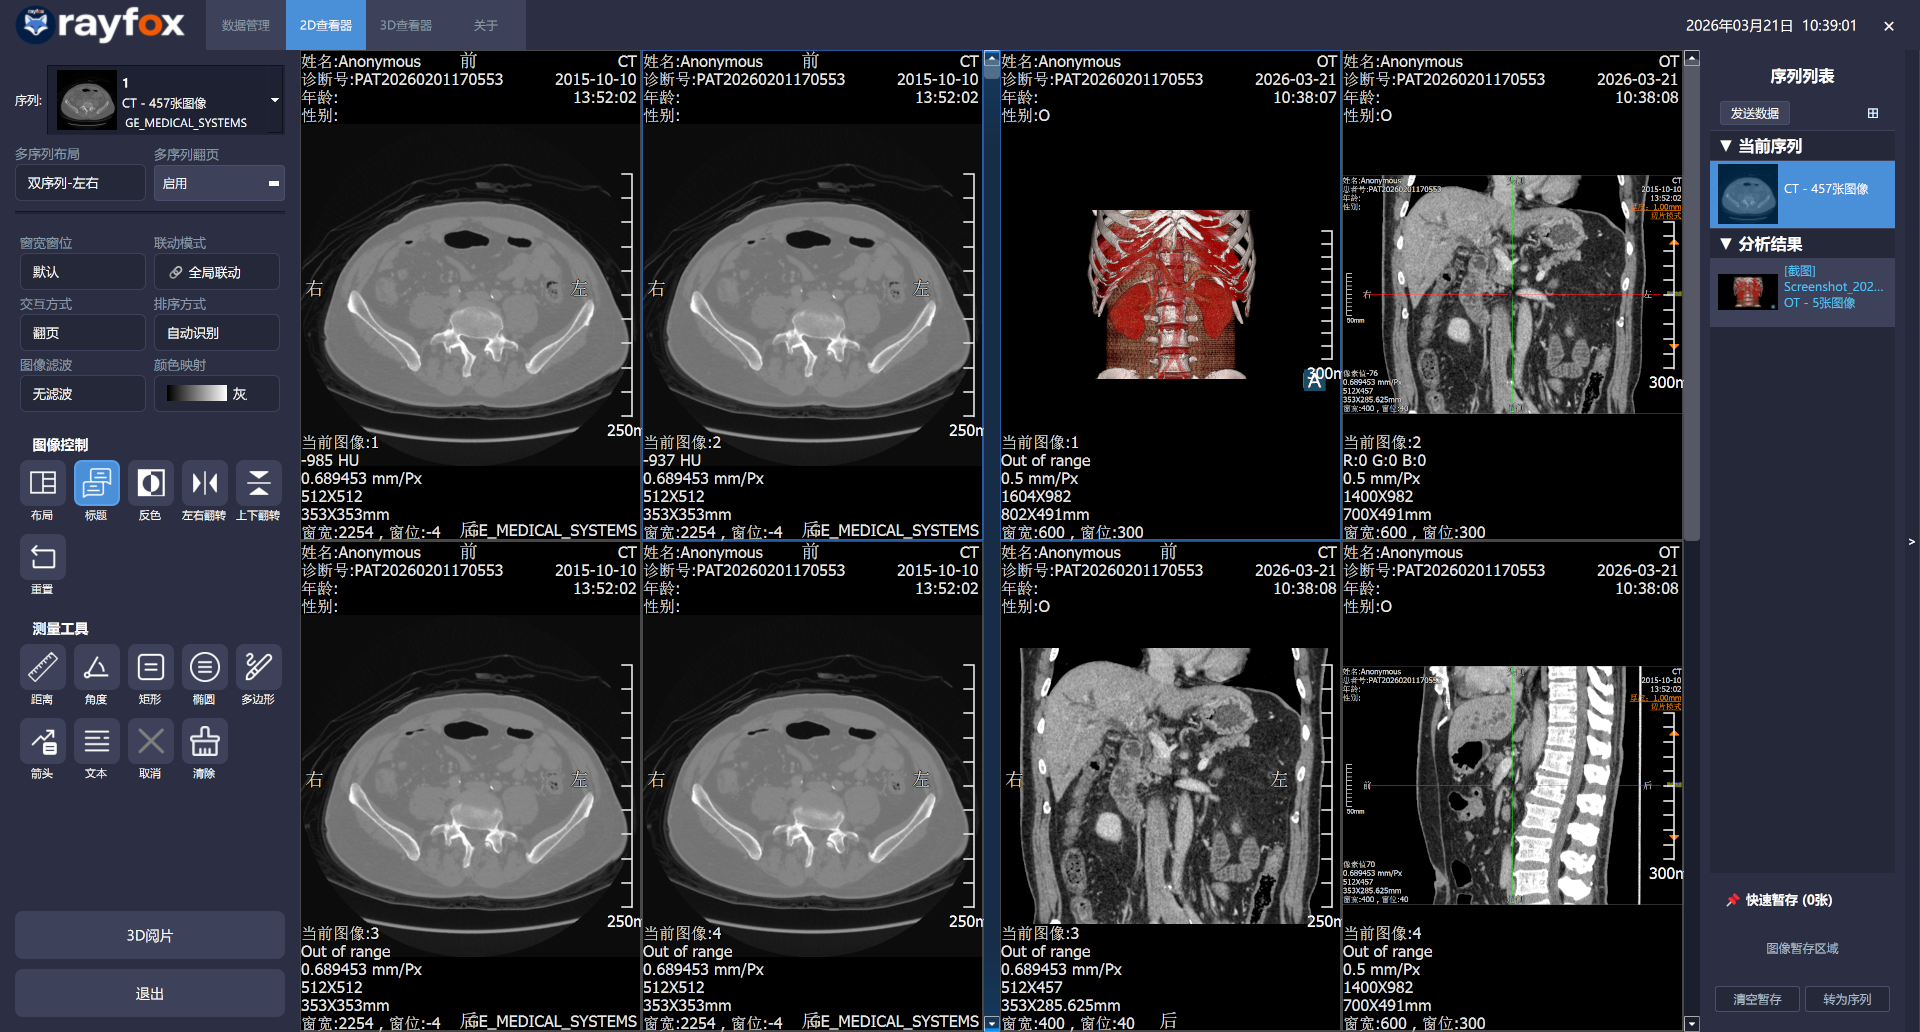

Windows macOS 2026年3月21日- 2D添加多序列阅片

- 2D/3D阅片添加右侧数据列表拖拽显示功能